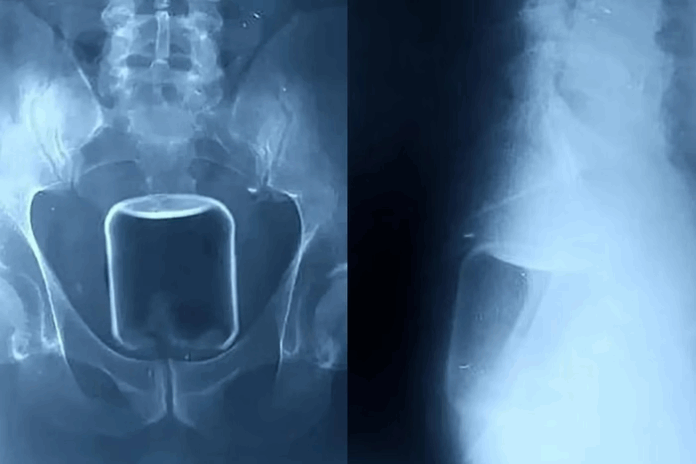

Em Nizhny Novgorod, na Rússia, um homem passou por uma cirurgia de alto risco para a remoção de um copo de vidro inserido no intestino pelo ânus durante um ato sexual. Além do copo, os médicos também retiraram um preservativo e lubrificante. O procedimento foi necessário para evitar complicações graves, como hemorragias fatais ou danos irreparáveis aos órgãos internos.

O paciente precisou ser submetido a uma intervenção cirúrgica após exames indicarem que o copo estava alojado na parte superior do reto e avançava em direção ao intestino superior. Segundo os médicos responsáveis, caso o frasco tivesse se quebrado dentro do organismo, as consequências poderiam ter sido fatais devido à possibilidade de hemorragias severas.